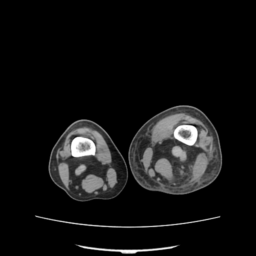

![]() |

| (a) | (b) | (c) | (d) |

Unsupervised Categorization: Our category discovery clusters are generally visually coherent within the cluster and size-balanced across clusters. However, image clusters formed only based on text information (of radiology reports) are highly unbalanced [49], with three clusters inhabiting the majority of images. Note that our method imposes no explicit constraint on the number of instances per cluster. Fig. 6 shows sample images and their top-10 associated key words from two randomly selected clusters (more results are provided in the supplementary material). The LDPO clusters are found to be clinically or semantically related to the corresponding key words, which describe presented anatomies, pathologies (e.g., adenopathy, mass), their associated attributes (e.g., bulky, frontal) and imaging protocols or properties.

The category discovery clusters employing our LDPO method are found to be more visually coherent and cluster-wise balanced in comparison to the results in [49] where clusters are formed only from text information ( radiology reports). Fig. 7 Left shows the image numbers for each cluster from the AlexNet-FC7-Topic setting. The numbers are uniformly distributed with a mean of 778 and standard deviation of 52. Fig. 7 Right illustrates the relation of clustering results derived from image cues or text reports [49]. Note that there is no instance-balance-per-cluster constraints in the LDPO clustering. The clusters in [49] are highly uneven: 3 clusters inhabit the majority of images. Fig. 6 shows sample images and top-10 associated key words from 5 randomly selected clusters (more results in the supplementary material). The LDPO clusters are found to be semantically or clinically related to the corresponding key words, containing the information of (likely appeared) anatomies, pathologies (e.g., adenopathy, mass), their attributes (e.g., bulky, frontal) and imaging protocols or properties.